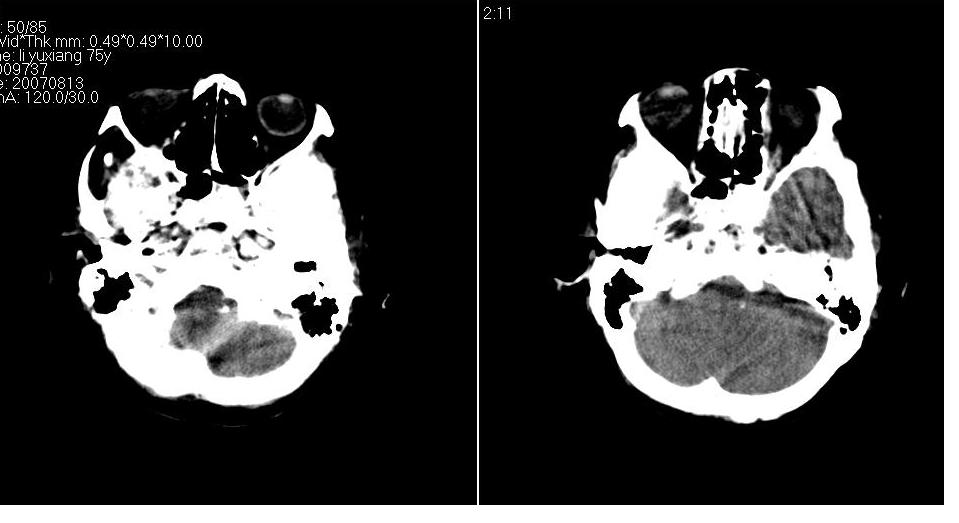

以下是引用川北影像在2007-8-14 15:33:00的发言:[br]1、右侧颞叶脑挫裂伤伴血肿形成。[br]2、右侧额颞顶部硬膜下血肿伴大脑廉下疝形成。

以下是引用gaoshengjiang在2007-8-14 16:30:00的发言:[br]大家都认为右侧颞叶脑挫裂伤伴血肿形成;右侧额颞顶部硬膜下血肿伴大脑廉下疝形成;蛛网膜下腔出血。 但硬膜下血肿、脑内血肿量不多,而大脑廉下疝明显,右侧颞叶类圆形高密度灶,周围轻度水肿,呈蟹足状,考虑脑内占位所致脑内血肿、突然晕倒、硬膜下血肿、颞叶脑挫裂伤等一系列改变。[br][br] [br]

以下是引用拾荒者在2007-8-14 21:59:00的发言:[br][quote]以下是引用gaoshengjiang在2007-8-14 16:30:00的发言:[br]大家都认为右侧颞叶脑挫裂伤伴血肿形成;右侧额颞顶部硬膜下血肿伴大脑廉下疝形成;蛛网膜下腔出血。 但硬膜下血肿、脑内血肿量不多,而大脑廉下疝明显,右侧颞叶类圆形高密度灶,周围轻度水肿,呈蟹足状,考虑脑内占位所致脑内血肿、突然晕倒、硬膜下血肿、颞叶脑挫裂伤等一系列改变。[br][br] [br]